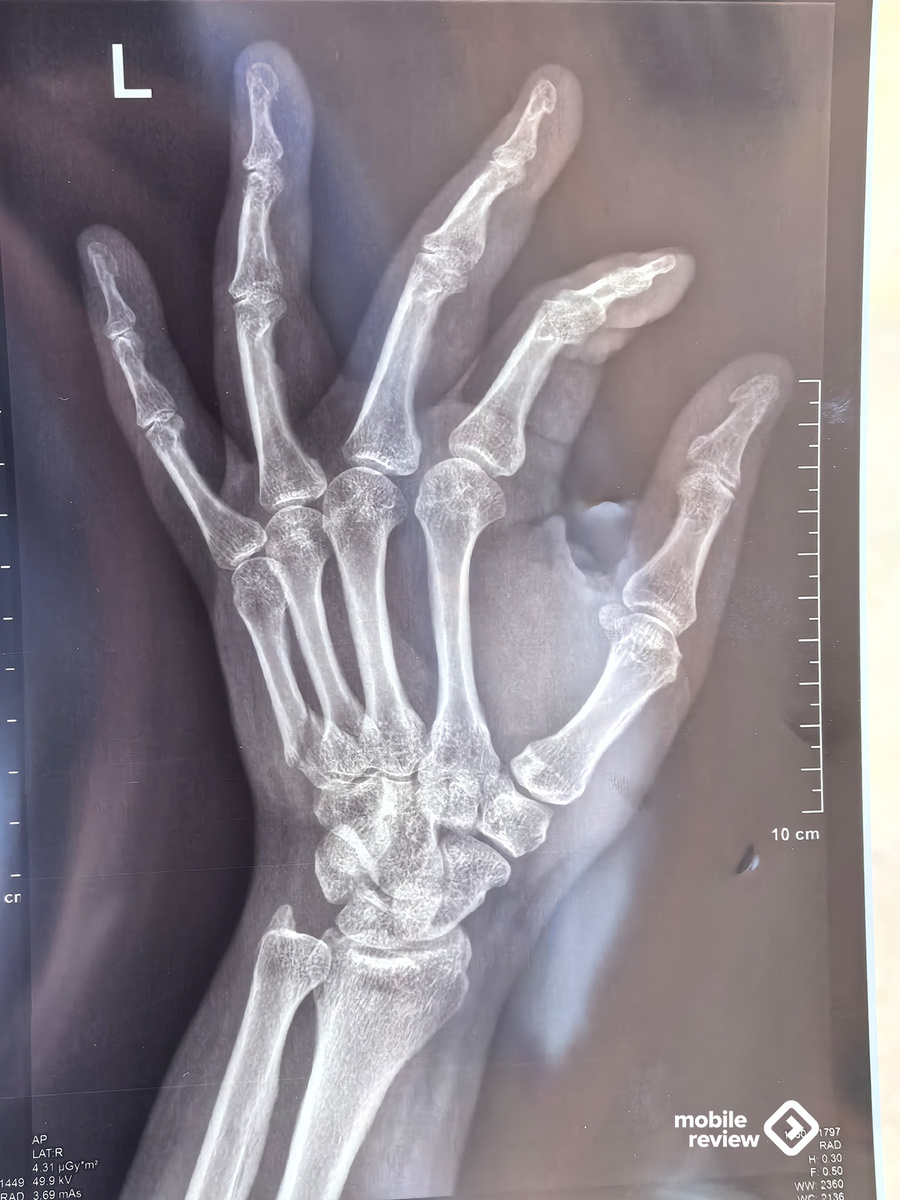

Московские пробки, в такси обзваниваю места вокруг, где мне могут сделать рентген, чтобы оценить степень повреждений. Пока ситуация 50 на 50, подвижность руки полная, но есть припухлость и болевые ощущения. После рентгена становится понятно: перелом и небольшое смещение.

Расписание уже полетело к чертям, но нужно попасть на презентацию от МТС, тем более что врач-травматолог примет меня только позже. Пообщался на презентации, успел даже подписать свою старую книгу для коллеги, показал снимок руки паре товарищей. Развлекался. После врача закончил вечер еще и тем, что провел почти часовой эфир, не стал его отменять. Насыщенный день.

До эфира был травматолог, обсуждение, что и как делать, отказался от восстановления эстетики, в будущем будет небольшая вмятина на руке. Поставили гипс на четыре недели, через неделю нужно снова идти на рентген и смотреть, как срастается кость.

Оставили несколько пальцев без гипса, посоветовали, как работать на компьютере и как точно не стоит, учусь жить заново в новых условиях. Жизнь с ограниченно доступной рукой довольно удивительна — совсем другие возможности и эмоции. Пишу этот текст на второй день с гипсом, ожидал, что все будет намного хуже. Тем не менее, рука елозит по клавиатуре, текст как-то набирается.